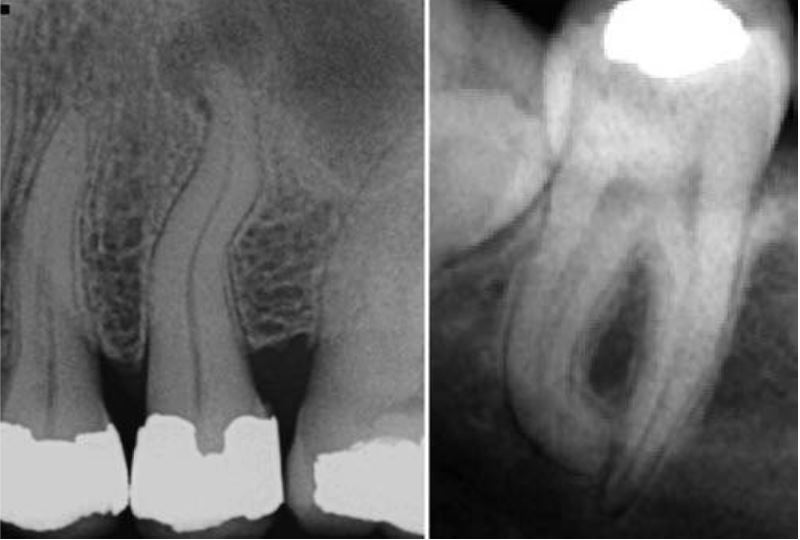

Rãnh nướu khẩu cái (palatogingival groove)

Là một khiếm khuyết xảy ra chủ yếu ở răng cửa bên hàm trên. Rãnh bắt đầu từ đường nối cingulum với 1 trong 2 gờ bên mặt trong, chạy xuống và mở rộng về phía chân răng. Rãnh nướu khẩu cái góp phần quan trọng gây bệnh nha chu bởi vì cement không thể phủ lên và dây chằng nha chu không thể bám vào phần đó.